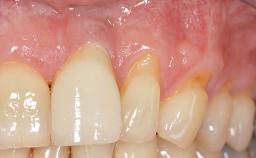

Implant Placement in the Esthetic Zone and Coverage of Multiple Gingival Recessions

This case illustrates use of a modified ‘tunnel’ technique, which has been shown to be highly effective in root coverage procedures. The tunnel technique is used to achieve soft-tissue augmentation across the anterior area, including the planned implant site, using collagen matrix as grafting material. The patient is a 47-year-old woman with high esthetic expectations. Her main concern was the appearance of the anterior teeth and their “elongation”.

Soft Tissue Anatomy Intact Defective

Soft Tissue Contour and Volume Significantly deficient